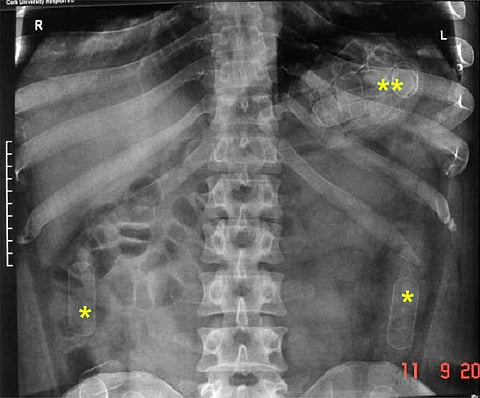

त्यानुसार जे. जे. रुग्णालयात त्याची क्ष-किरण तपासणी व सोनोग्राफी करण्यात आली. त्यावेळी त्याच्या पोटात कॅप्सूल असल्याचे निष्पन्न झाले. त्यानंतर डॉक्टरांनी त्याच्या पोटातून कोकेन भरलेल्या 53 कॅप्सूल काढल्या. जप्त करण्यात आलेल्या 534 ग्रॅम कोकेनची किंमत एक कोटी 60 लाख रुपये आहे.